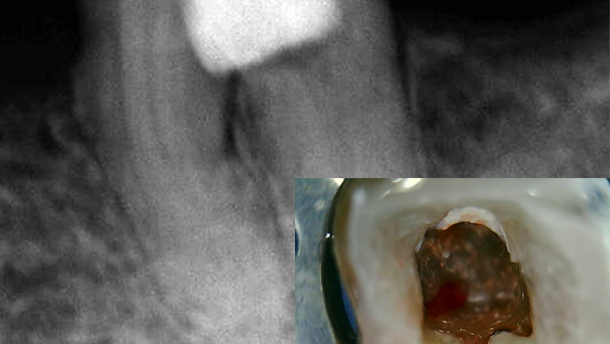

Paciente del género femenino, de 47 años, que se presentó con cuadro clínico de extensa perforación iatrogénica en la región de la furca del elemento dental #36 (Figuras 1 y 2), asociado con pérdida ósea radiográficamente, fístula vestibular y dolor a la palpación. La paciente relató haberse sometido previamente a una intervención de urgencia en este diente por otro profesional, dado que presentaba un dolor agudo característico de pulpitis.

La obturación se realizó por la técnica termomecánica híbrida de Tagger (Figura 3), mediante el empleo de GutaCondensor (Maillefer/Suiza), conos de gutapercha TP (Dentsply, Brasil) y cemento obturador a base de M.T.A. Fillapex (Angelus, Brasil) (Figura 4). Tras la termocompactación, se realizó el corte de la obturación, condensación vertical con el uso de calcadores en frío; y nuevamente se limpió y obturó la región de la perforación con hidróxido de calcio.

A los 15 días, se procedió al sellado de la región de la perforación, constatando primero la adecuada posibilidad de secado de la zona. La oburación de la perforación se realizó con el material MTA Repair HP (Angelus, Brasil), previamente preparado conforme a la recomendación del fabricante, siendo el mismo introducido con el uso de Aplicador de MTA (Angelus/Brasil). Se utilizaron criterios clínicos y radiográficos para determinar la correcto obturación del material (Figuras 4 y 5); se empleó cemento de ionómero de vidrio (Vitremer/3M/EUA) para proteger la región sellada (Figura 6). Tras la restauración provisoria, se observó radiográficamente que el maerial MTA Repair HP había conseguido un adecuado sellado de la región de la furca, así como un postoperatorio sin problemas.

En la evaluación realizada dos meses después, se observó neoformación ósea en la región de la furca y ausencia de sintomatología (Figura 7).